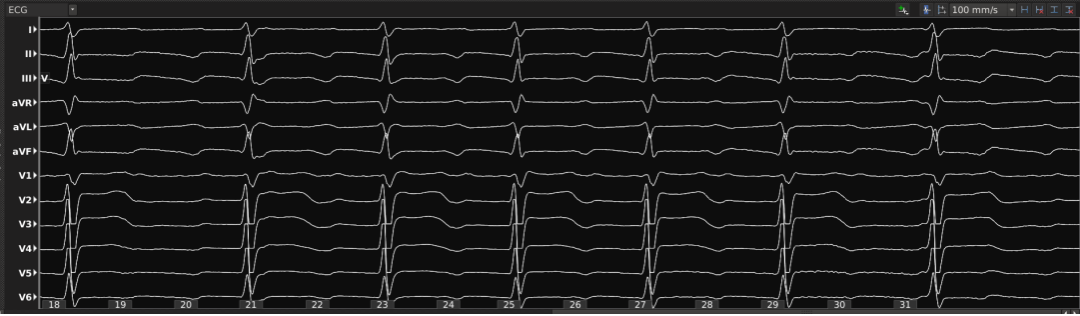

AFL ECG EGM

DriectSense局部阻抗指示贴靠与消融有效性

关键峡部放电有效终止房扑